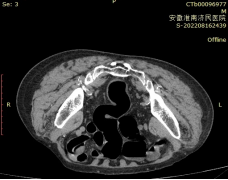

检测方法:常规准备,取左侧卧位肛门插管,缓注碘造影剂稀释液约100ml(碘剂∶生理盐水=1∶2),见阴道有液体流出,行俯卧位盆部扫描,将断层图像原始数据进行多平面重建(MPR)、三维重建(3D),展示瘘管形态。

C T 图 像

断层图像:直肠(黄色箭头)、阴道(黑色箭头)

瘘管(红色箭头)